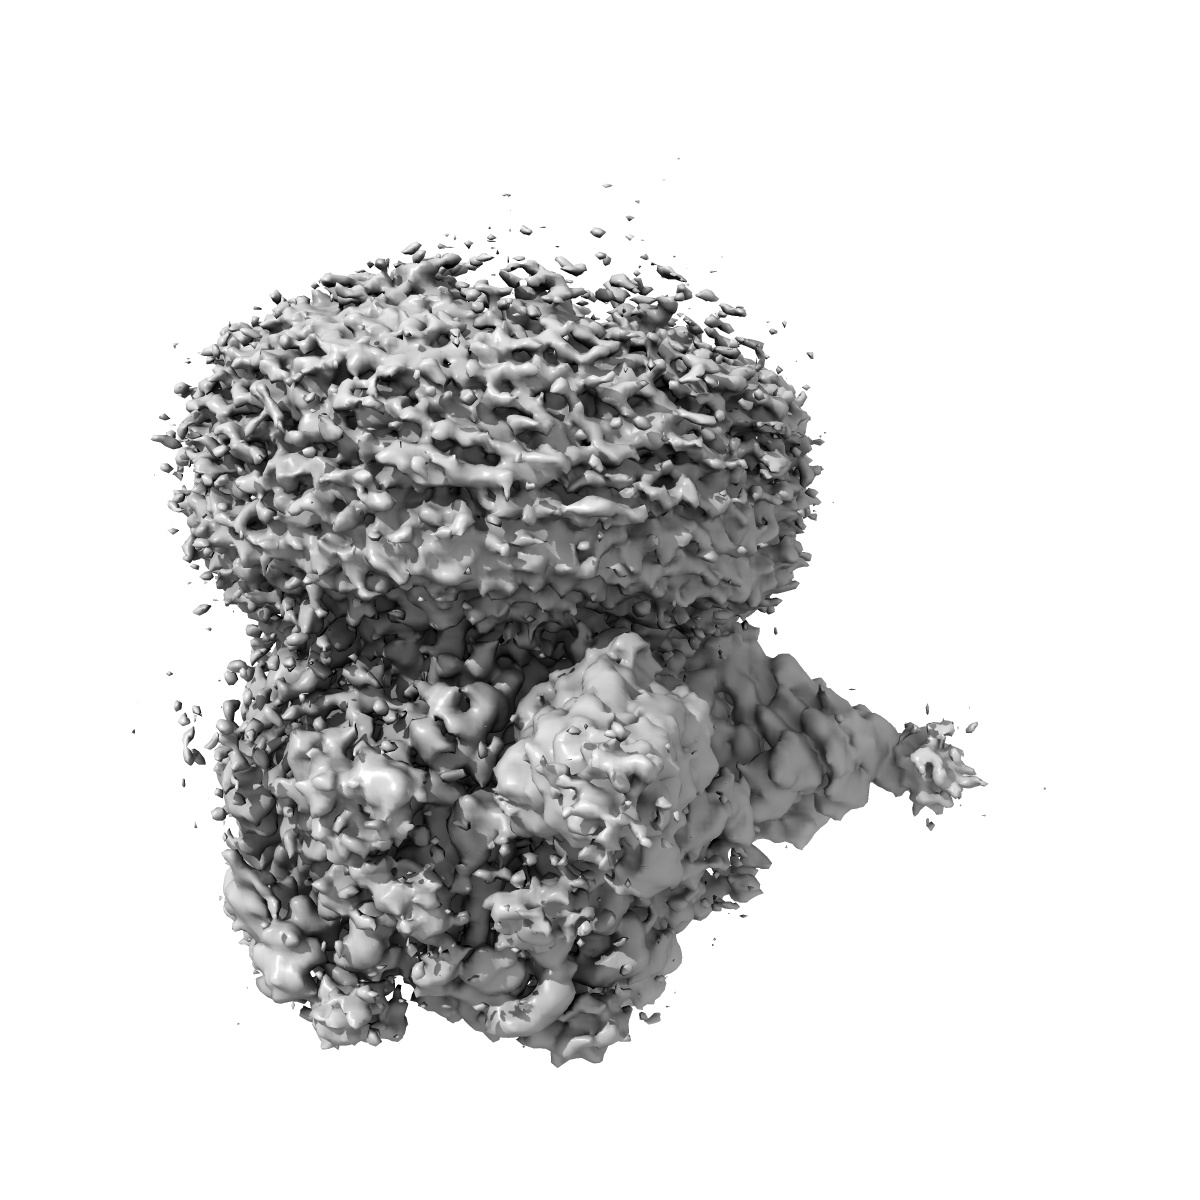

Cryo-EM structure of human full-length extrasynaptic alpha4beta3delta GABA(A)R in complex with THIP (gaboxadol), histamine and nanobody Nb25

Single-particle2.9 Å

Sample: Human full-length extrasynaptic alpha4beta3delta GABA(A)R in complex with THIP (gaboxadol), histamine and nanobody Nb25